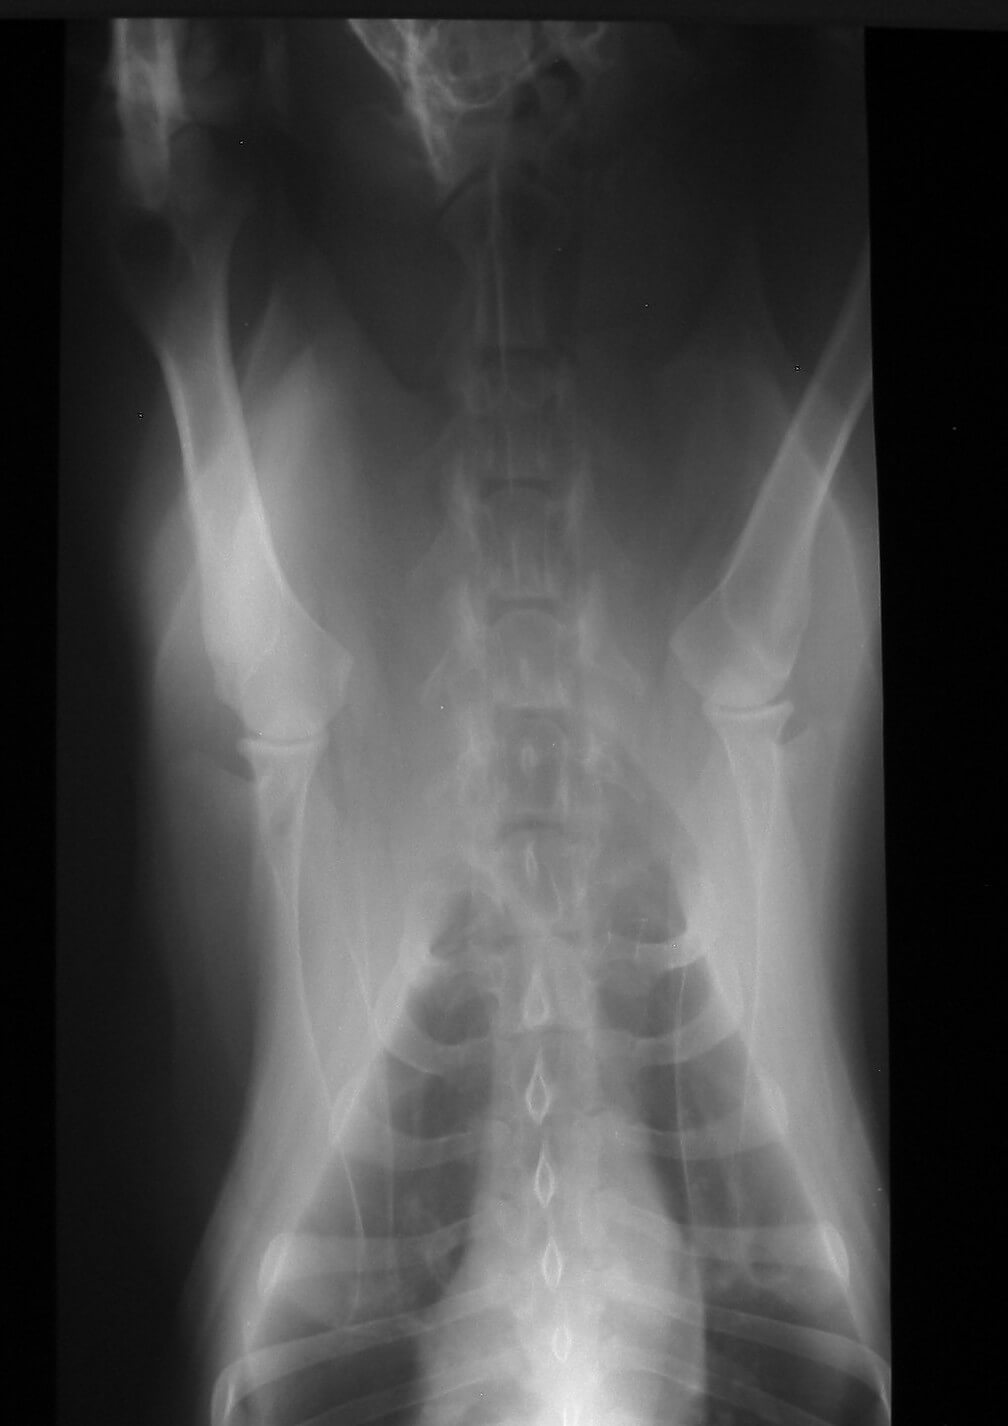

Digital Radiography

At Animal Haven Veterinary Clinic of Socorro in Socorro, NM, we are proud to be on the cutting edge of medical technology. Radiology is a technique and diagnostic tool we use to look inside the body in a completely non-invasive way. X-rays allow us to create images of all the body's organs. In other words, the use of radiology gives us a view of the internal organs in your pet's body that we otherwise could not see. It's an important diagnostic tool that helps veterinarians detect and prevent illnesses.

The images produced by digital radiography are of much better quality than film radiographs and can be manipulated digitally, giving us the best possible radiographic information to help us diagnose your pets.

The use of radiology is safe, and our entire staff is highly trained. It is our goal to provide your pets with the highest level of medical care possible, and this is just one of the many ways we achieve that.